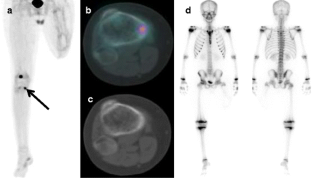

Fig. 1

Fig. 2

Fig. 3

Fig. 4

Fig. 5

Fig. 6